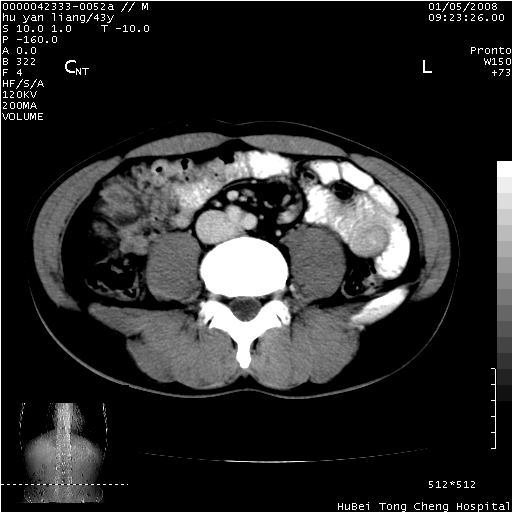

患者 男,43岁。右上腹不适1年余。既往有“肝右叶肝脓肿”病史,经保守治疗后痊愈。

b超提示:1)肝右叶肝内胆管结石。2)肝右叶占位性病变待排。

上中腹部ct轴位平扫+增强扫描(层厚10mm,螺距1.0,重建间隔10mm),图像如下:

肝右叶钙化灶,考虑为肝脓肿后遗症。

肝右叶后段团块状钙化灶,结合病史考虑肝脓肿痊愈后表现。